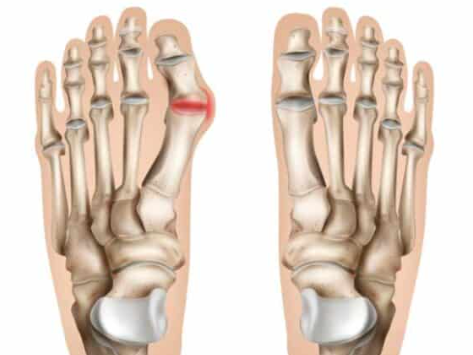

무지외반증("hallux valgus”)이란?

무지외반증은 발가락 통증을 일으킬 수 있는 특정한 상태입니다. 이는 발가락으로 통증을 유발할 수 있는 신경 주위의 조직이 두껍고 확장되는 경우 발생합니다. 이는 특히 세 번째와 네 번째 발가락 사이의 발의 앞부분에서 심한 불편함을 초래할 수 있습니다.

무지외반증 원인

1. 유전적 요인:

일부 사람들은 무지외반증을 유전적으로 가질 수 있습니다. 만일 가족의 어느 누구가 무지외반증을 가지고 있다면, 이를 상속할 가능성이 높아집니다.

2. 부적절한 신발:

협소하거나 높은 힐을 가진 신발을 자주 신으면 발가락이 압력을 받고 무지외반증이 발생할 가능성이 높아집니다. 신발이 발에 맞지 않는 경우 발가락이 압력을 받고 비뚤어질 수 있습니다.